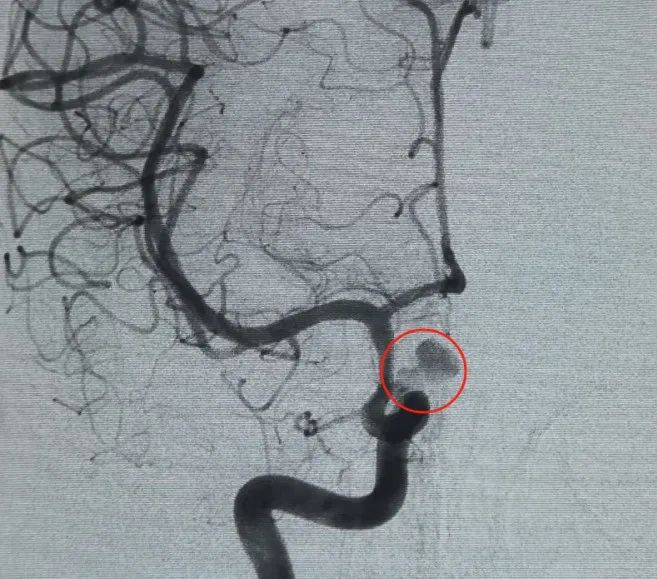

Diagnosis: Left internal carotid artery C6 segment ophthalmic artery aneurysm

A Perfiller® 3 mm × 6 cm expansible coil and a Perfiller® 3 mm × 2 cm expansible coil were then placed to complete neck occlusion. Subsequently, a Nuva® Flow Diverter (TJED-D-5.0-16) was delivered and deployed across the aneurysm neck. Follow-up angiography in both anteroposterior and lateral views confirmed excellent coverage, good wall apposition, and clear radiopacity, with marked contrast stagnation.

The procedure was completed smoothly with no complications, and the patient recovered without neurological deficits.